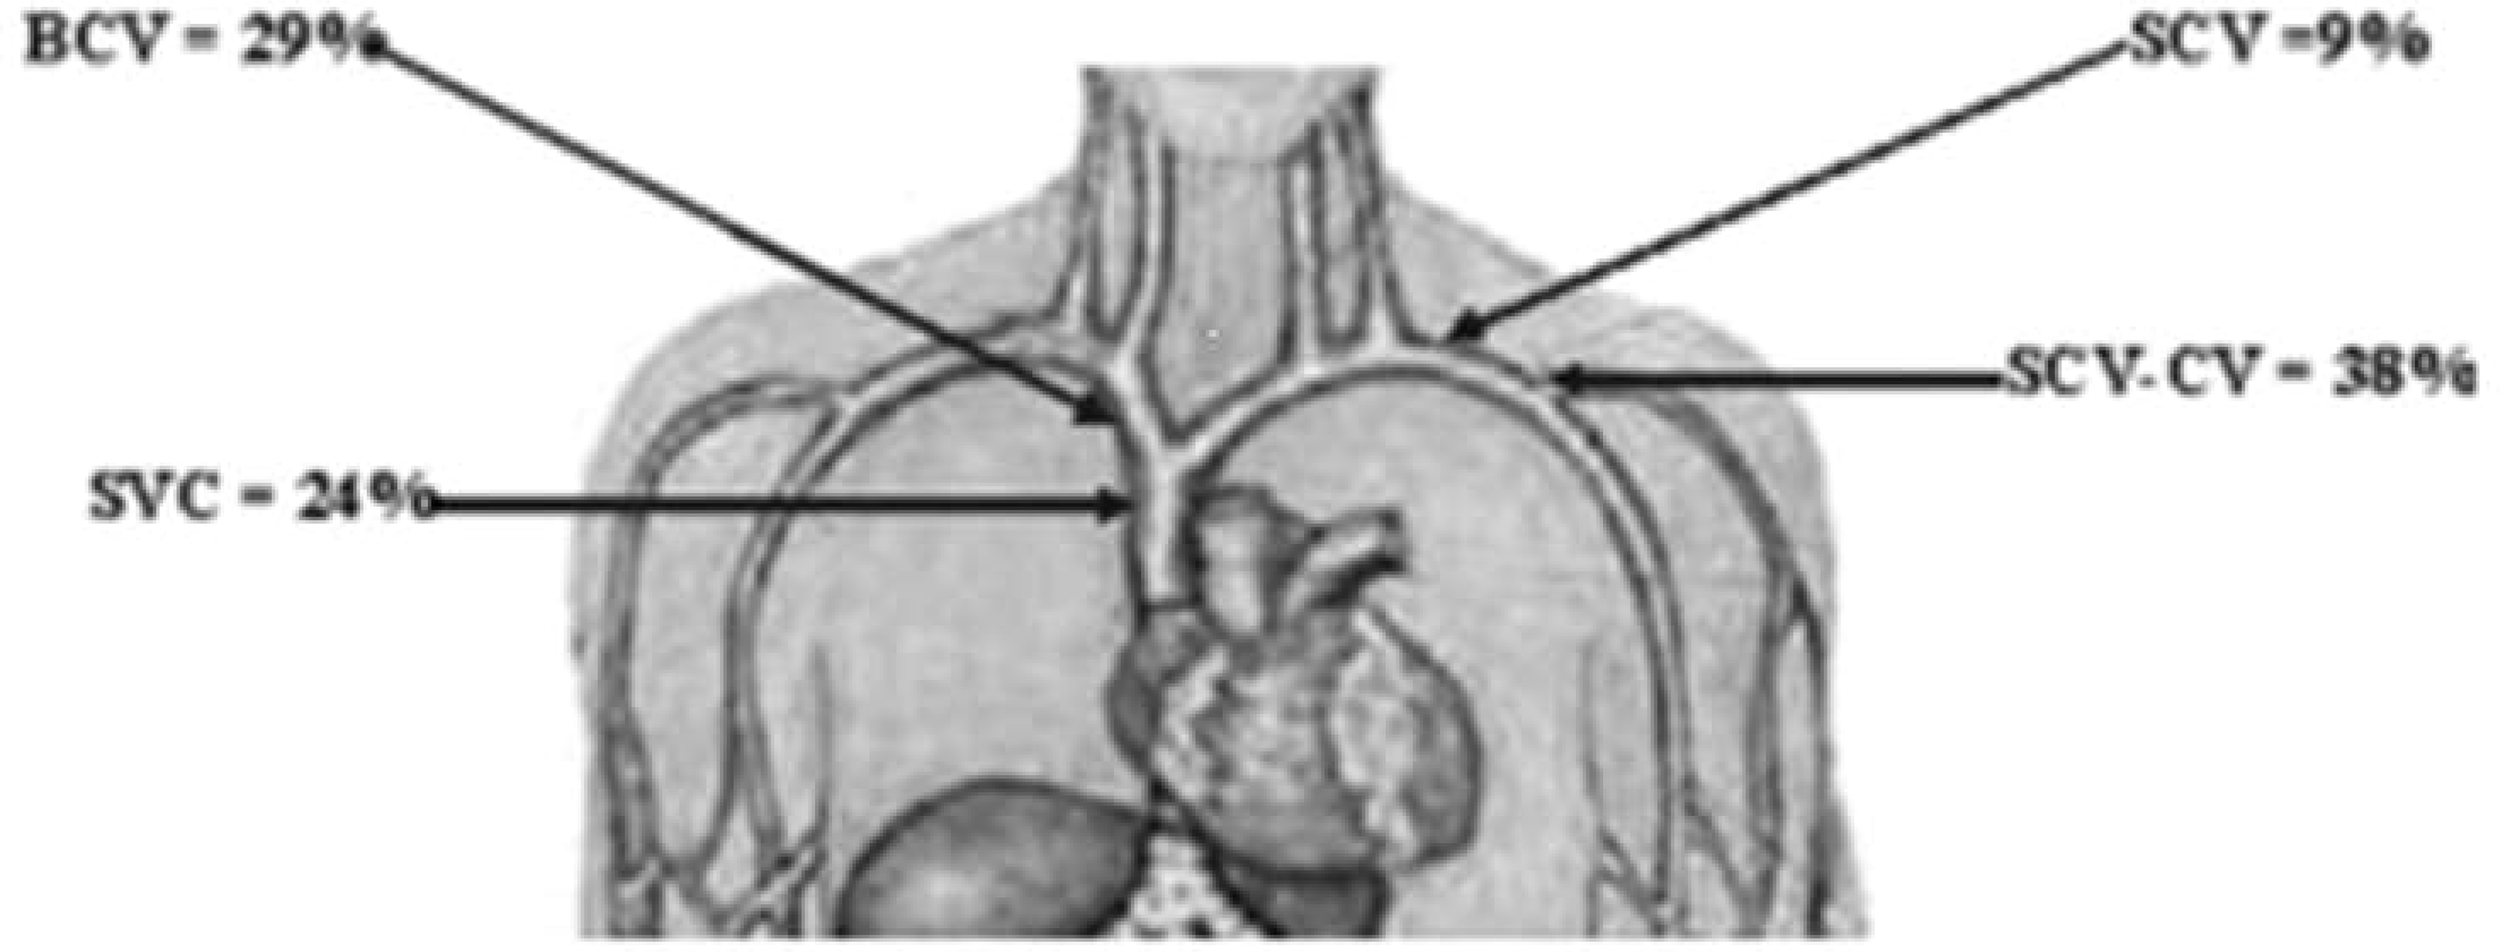

McCrae et al. detailed the anatomic distribution of CVS based on the study of 133 HD patients with venogram-confirmed CVS (11). According to the authors, most CVS lesions are located at the junction of the subclavian and cephalic veins (38%), followed by the brachiocephalic vein (29%), and then the superior vena cava (24%). The free segment of the subclavian vein is the least involved (Figure 1) (11).

Figure 1

Anatomic distribution of CVS. CVS, central vein stenosis; SCV, subclavian vein; BCV, brachiocephalic vein; SVC, superior vena cava; SCV-CV, SCV, and subclavian-cephalic vein junction. Image is derived from MacRae et al. (11).